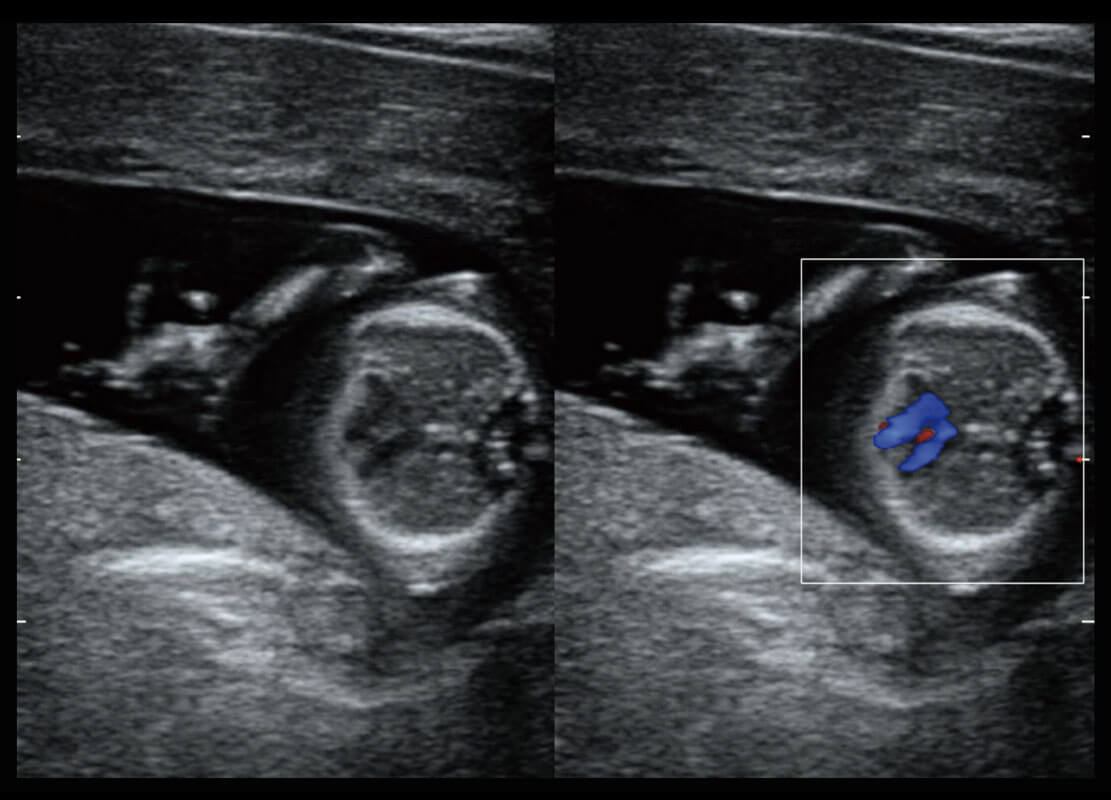

乳腺超声 / 新生儿

P60搭载宽频带线阵探头、宽景成像、弹性成像技术,为您提供乳腺应用方案。P60支持高频相控阵探头、线阵探头、腹部高频探头、腹部微凸探头等,丰富的探头群搭载敏感的彩色血流成像,适用于新生儿多种脏器检测要求,满足新生儿筛查需求。

• 新生儿肝血管癌

• 新生儿心脏